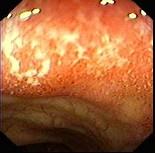

女性,26岁,反复排粘液血便,腹痛6年,便后腹痛可部分缓解,无里急后重感,无发热。胃纳较好;左侧腹有轻压痛,无反跳痛,肝脾不大。 肠镜如图,惯于本病的病理...

问题 女性,26岁,反复排粘液血便,腹痛6年,便后腹痛可部分缓解,无里急后重感,无发热。胃纳较好;左侧腹有轻压痛,无反跳痛,肝脾不大。 肠镜如图,惯于本病的病理改变,正确的是 ( )

选项 A.病变呈节段性 B.多数在直肠和乙状结肠 C.常呈肠全层炎 D.活动期有大量中性粒细胞和嗜酸性粒细胞浸润 E.裂隙溃疡,呈缝隙状,可深达肌层

答案 BD